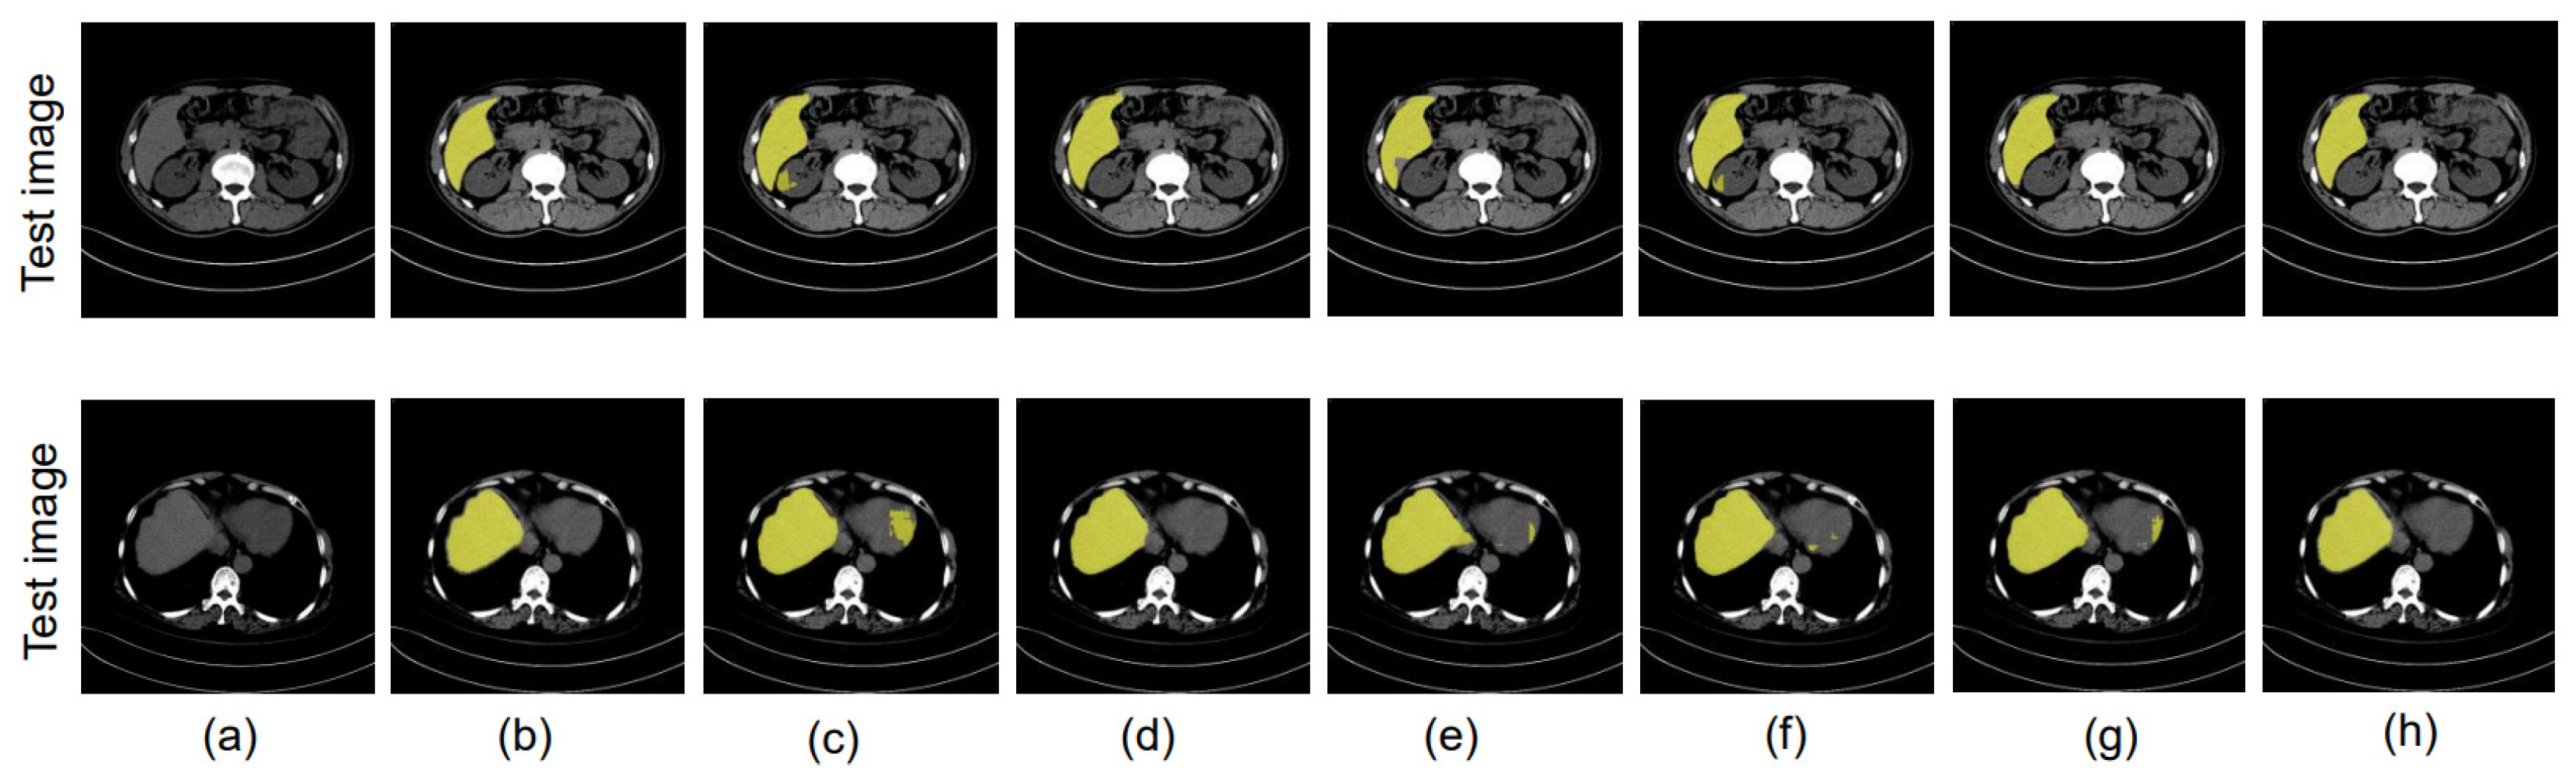

4.8.2. Same Datacenter and Different Phase